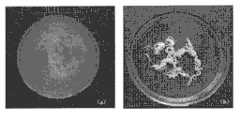

图1显示了白糊精对ICPC抗溃散性能的影响,其中,(a)为不含白糊精的ICPC(b)为含白糊精ICPC。Figure 1 shows the effect of white dextrin on the anti-collapse performance of ICPC, where (a) is ICPC without white dextrin (b) is ICPC with white dextrin.

在抗溃散剂白糊精和促凝剂磷酸氢二钠的双重作用下,水相可注射磷酸钙骨水泥注射到液相后,形成线,掉落的粉渣较少,水体清澈;未加白糊精时,浆体注射到水中即可溃散,水体浑浊,如图1所示。采用X-射线衍射仪对实施例1的固化产物进行物相分析,结果如图2(e)所示,表明该体系的固化产物主要为羟基磷灰石,白糊精对固化产物组成无明显影响。黄糊精、英国胶、麦芽糊精加入后的效果与白糊精相同。Under the double action of the anti-collapse agent white dextrin and the coagulant disodium hydrogen phosphate, after the water-phase injectable calcium phosphate bone cement is injected into the liquid phase, a line is formed, the falling powder residue is less, and the water is clear; When white dextrin is used, the slurry will collapse when injected into water, and the water will be turbid, as shown in Figure 1. Adopt X-ray diffractometer to carry out phase analysis to the cured product of embodiment 1, the result is as shown in Figure 2 (e), shows that the cured product of this system is mainly hydroxyapatite, and white dextrin has no significant effect on the composition of cured product. Influence. The effect of adding yellow dextrin, British gum and maltodextrin is the same as that of white dextrin.